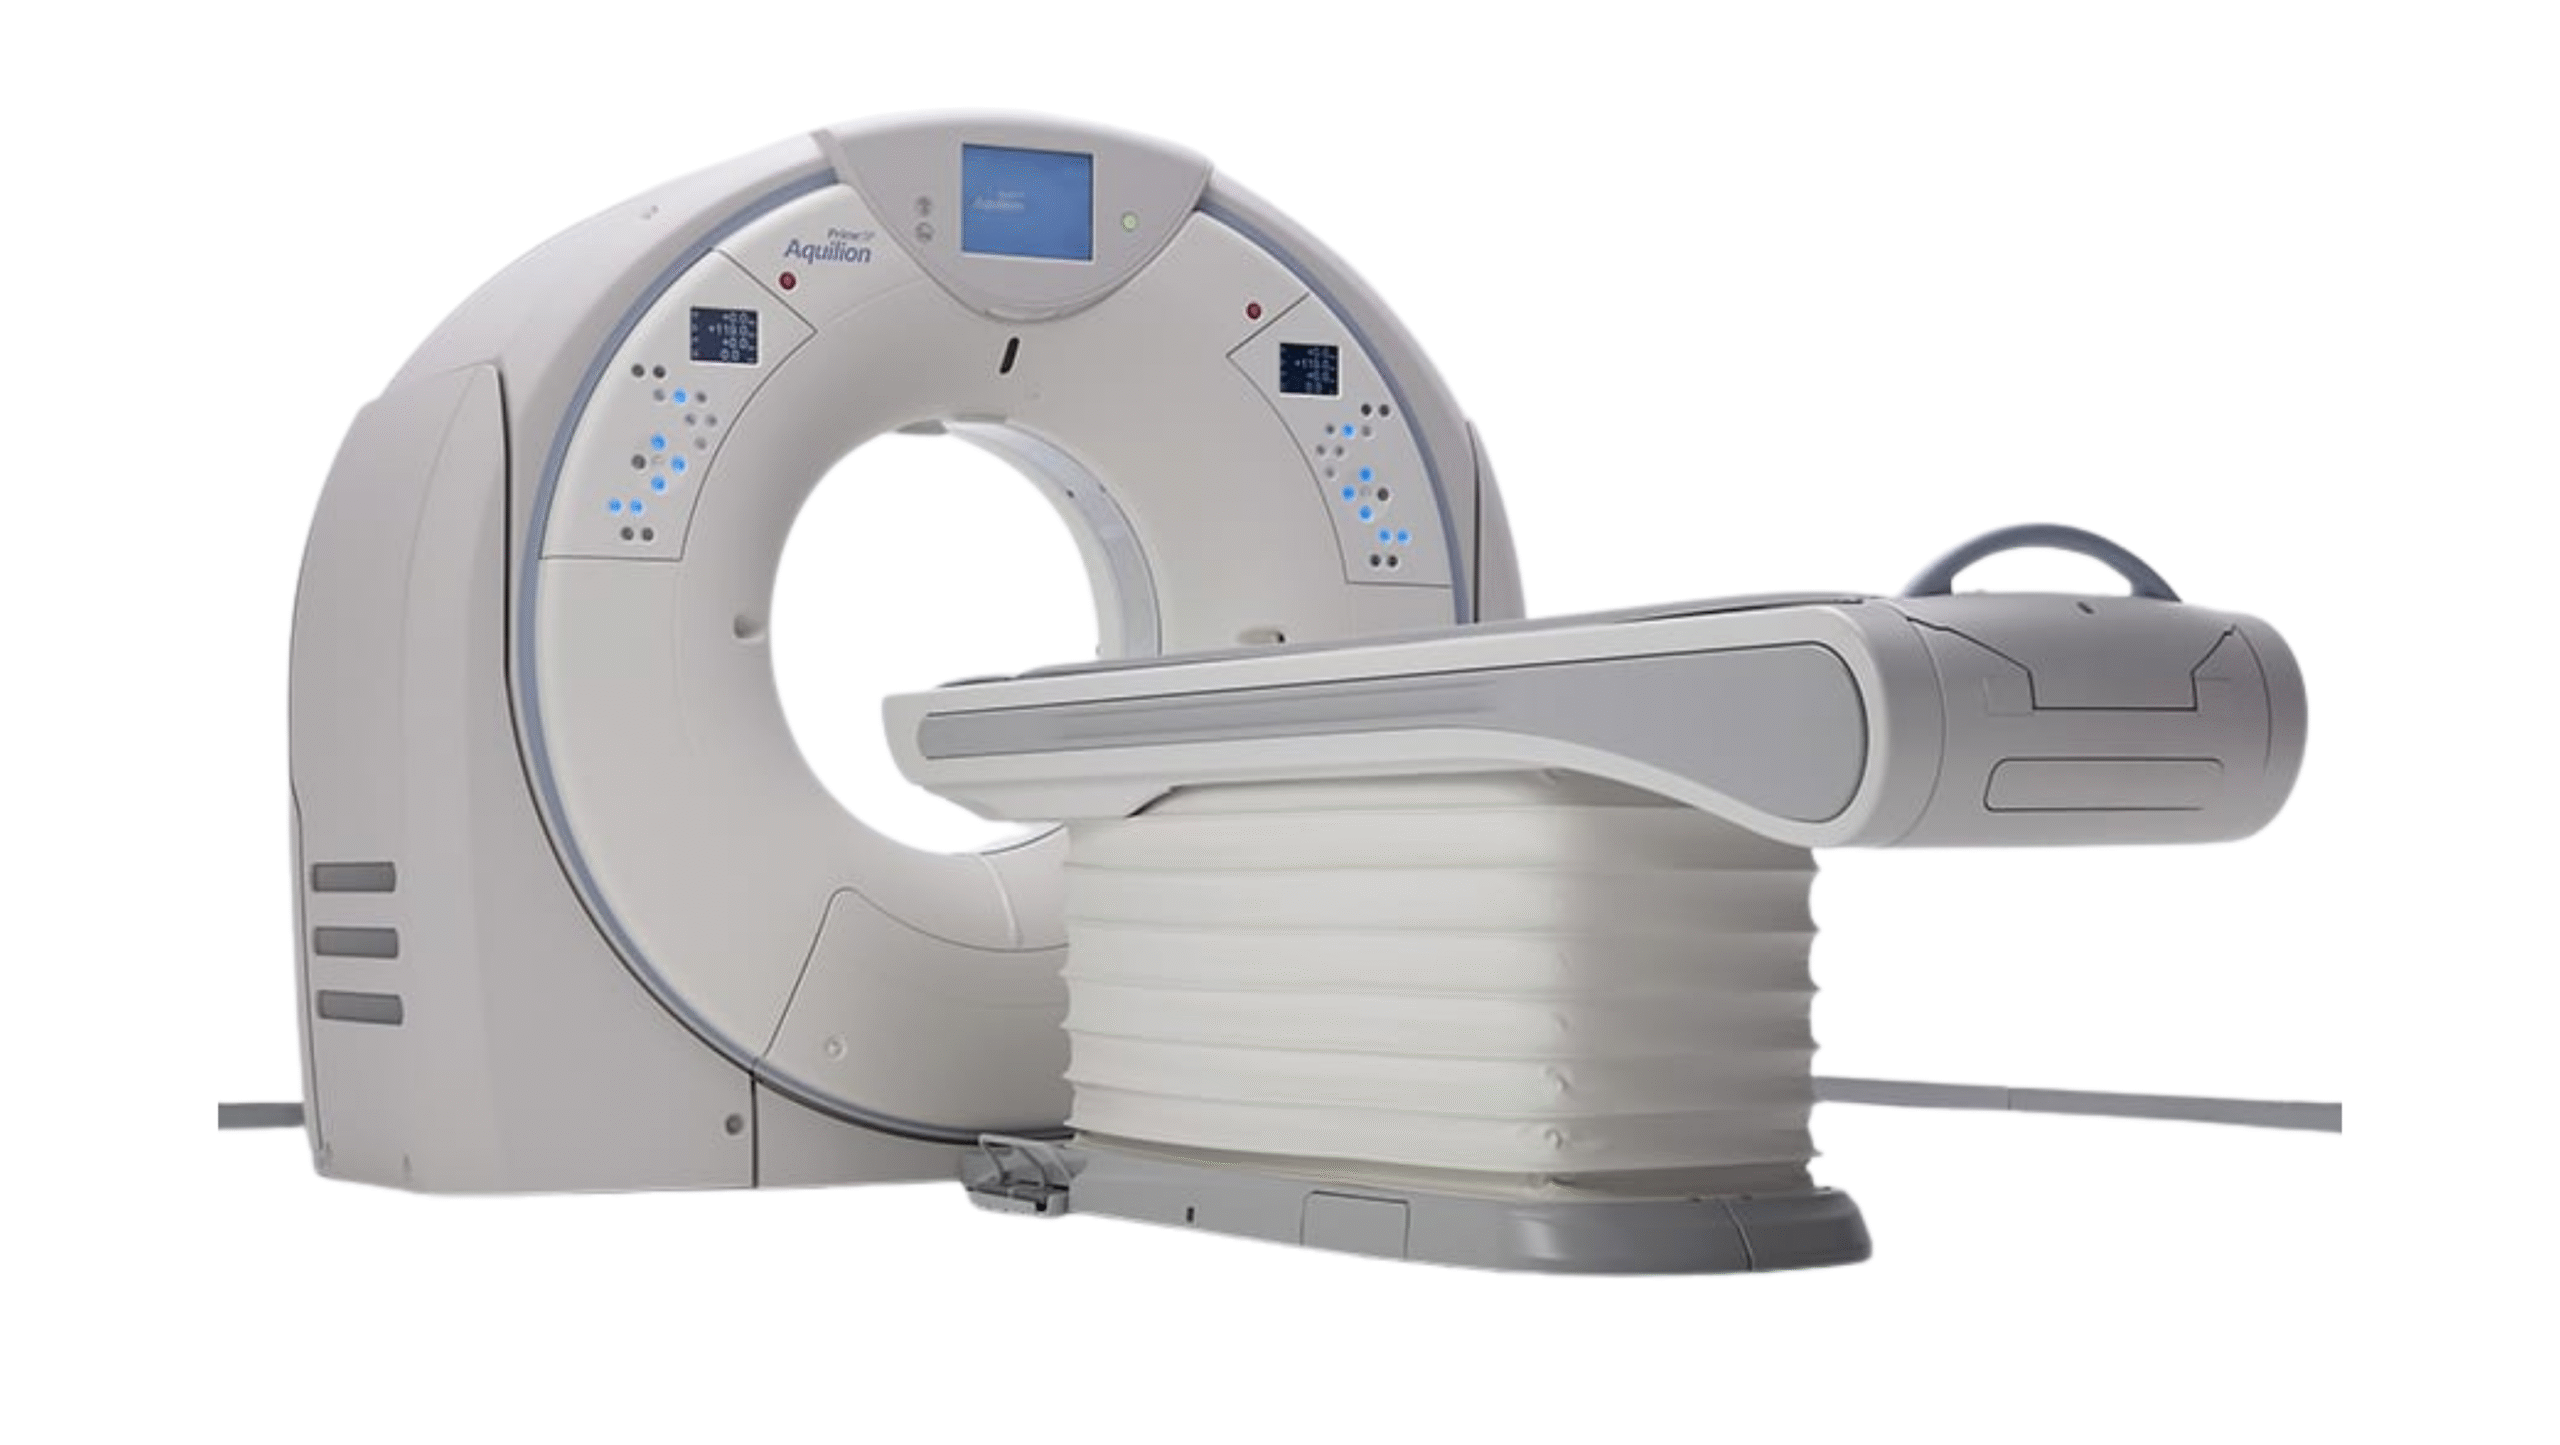

Products

We provide reliable service for our partners all around the globe. Offering well-known brands such as Fujifilm Healthcare, Carestream Health, Konica Minolta Healthcare and many others. Minimum order quantity is 1 pallet.